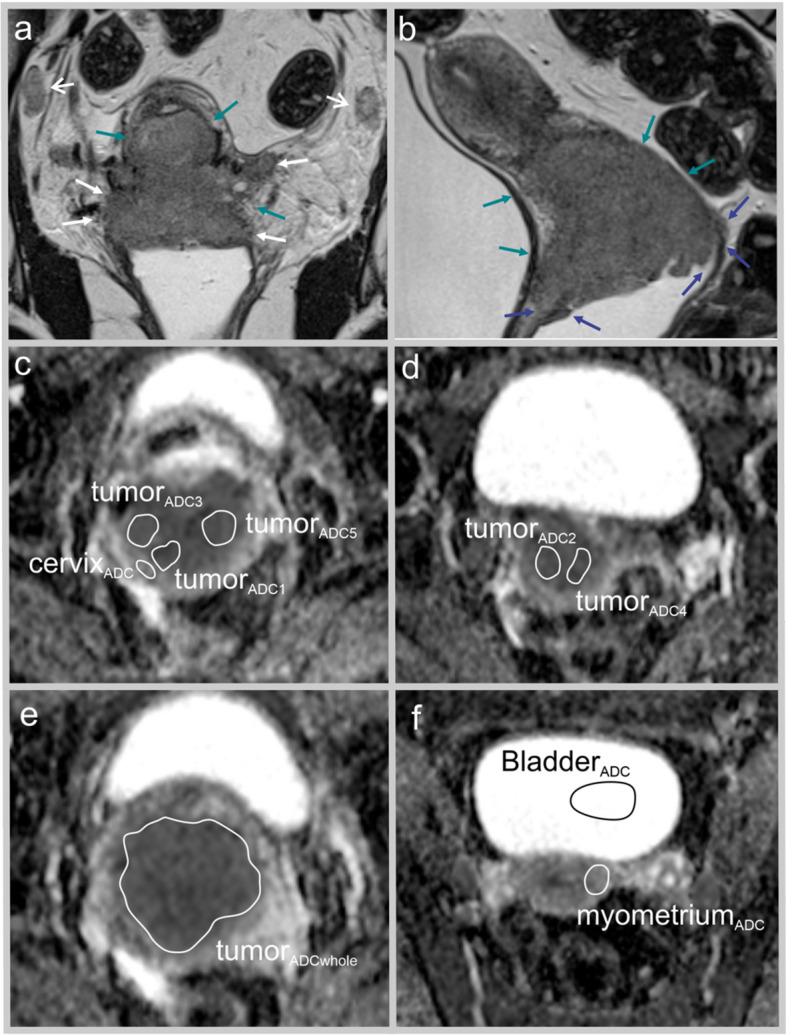

Pelvic MRI is essential for evaluating local and regional tumor extent in uterine cervical cancer (CC). Tumor microstructure captured by diffusion-weighted imaging (DWI) and apparent diffusion coefficient (ADC) markers may be closely linked to prognosis in CC.Purpose To explore whether primary tumor ADC markers predict survival in CC.Material and methods CC patients (n = 179) diagnosed during 2009-2020 with MRI-assessed primary maximum tumorsize ≥ 2 cm were included in this retrospective single-center study. Two radiologists read all MRIs independently, measuring mean tumor ADC values in manually drawn regions of interest (ROIs) and mean tumor ADC (tumorADCmean) from five measurements for the two readers was used. ADC from ROIs in the myometrium (myometriumADC), cervical stroma (cervixADC), and bladder (bladderADC) were used to calculate ADC ratios. ADC markers were explored in relation to the International Federation of Gynecology and Obstetrics (FIGO) (2018) stage, disease-specific survival (DSS), and recurrence/progression-free survival (RPFS).Results Inter-reader agreement for all ADC measurements was high (ICC:0.59-0.79). Low tumorADCmean predicted advanced FIGO stage (P = 0.04) and reduced DSS (hazard ratio (HR): 0.96, P < 0.001; AIC: 441). MyometriumADC/tumorADCmean yielded the best Cox regression fit (AIC = 430) among all tumor ADC markers. Patients with high myometriumADC/tumorADCmean had significantly reduced 5-year DSS for FIGO stage I, II, and III (P = 0.01, 0.004, and 0.02, respectively) and tended to the same for FIGO IV (P = 0.22).Conclusion Low tumorADCmean predicted reduced DSS in CC. High myometriumADC/tumorADCmean was the strongest ADC predictor of poor DSS and a marker of high-risk phenotype independent of FIGO stage.